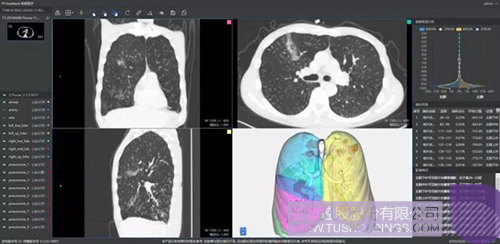

柏视医疗

推出的新冠肺炎辅助筛查系统借助AI技术可行之有效地辅助大规模新冠肺炎病例的影像筛查工作。同时基于肺部结构快速智能分割,让医生对肺部病变情况一目了然。还可结合临床征象,自动生成符合最新型冠状病毒指南的结构化图文报告,辅助医生大幅提升诊断效率,同时提高诊断准确性。